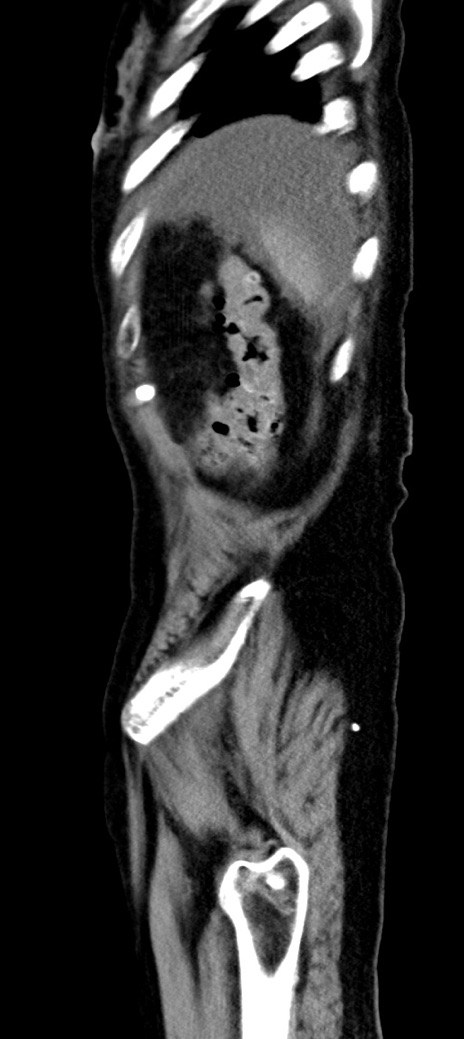

横断像

他院CT